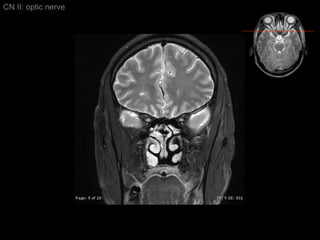

Intraocular segment 1 mm in length Ganglion cell axons exit globe CN II: optic nerve

Intraorbital segment 20-30 mm in length Extended posteromedially from back of globe to orbital apex (within intraconal space) CN2 longer than actual distance form optic chiasm to globe    allowing for eye movement CN II: optic nerve

Intraorbital segment Covered by 3 meningeal layers as brain  Subarachonoid space contains CSF    continue with suprasellar cistern CN II: optic nerve

Intracanalicular Segment Segment within bony optic canal  4-9 mm in length CN II: optic nerve

Intracanalicular Segment CN II: optic nerve Dura of CN2 fuses with orbital periosteum (Periorbita)

Intracranial Segment About 10 mm length from optic canal to chiasm Covered by pia and surrounded by CSF within suprasellar cistern CN II: optic nerve

Axial CT CN II: optic nerve

CN II: optic nerve Axial T2/ inferior to superior